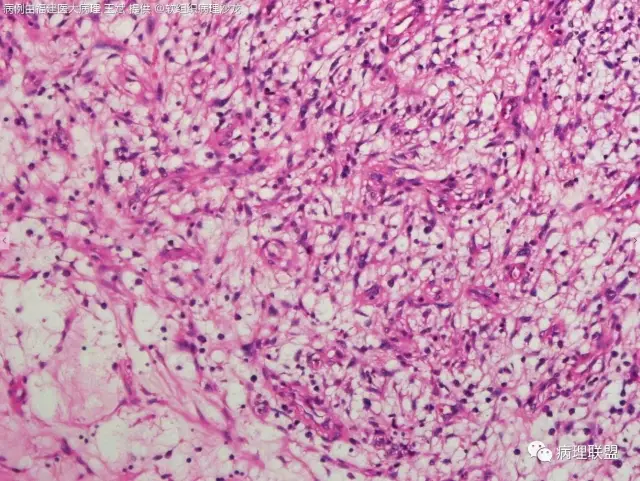

38岁,女性,手部小指背侧皮下肿物,3×2cm(病例由福建医大病理 王斌提供,致谢!)

血管瘤样纤维组织细胞瘤的肿瘤周围有淋巴细胞鞘,结节状分布,有假包膜,出血囊性变的为其主要特点,当然少数病例可以没有出血囊性变却出现粘液变。肿瘤细胞有一定异形性,属于低度恶性或交界性,最好做个FISH,看看有没有EWSR1-CREB1融合基因,刚查了一下,血管瘤样纤维组织细胞瘤还有另一种EWSR1-ATF1融合基因,无论是哪种,用EWSR1分离探针就可以检测